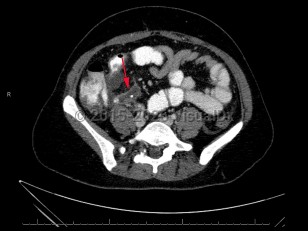

Inflammation begins within the appendiceal lumen and extends through the endothelial wall, leading to focal ischemia, tissue necrosis, and, in some instances, perforation. Perforation can lead to complications including generalized peritonitis and abscess formation.